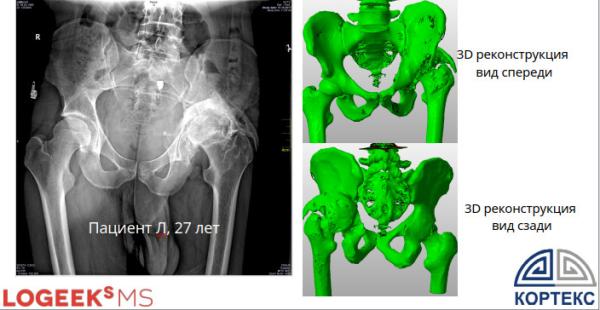

— Предоперационное планирование на 3D-моделях

Формирование данных об истинной геометрии дефекта с учетом плотности костной ткани

Предоперационное планирование на фантомах

Пластиковая модель костей таза позволяет физически продублировать оперативное лечение еще до операции.